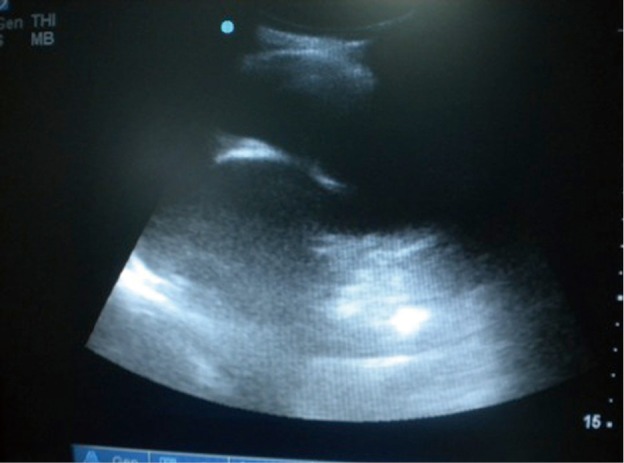

Figure 1.

Ultrasonographic appearance of the pleural effusion.

The most common and easiest method for investigating the presence of a pleural effusion in breast cancer patients is a chest X-ray (posteroanterior and lateral). Pleural ultrasonography (USG) may be used for the diagnosis of smaller quantities. USG is also helpful in determining the site of thoracentesis, especially when there is a small amount of collection (4).

The insertion sites for the prolonged pleural catheters (JP® Drain) were determined with thoracic ultrasound prior to the procedure in order to find a position for easy access. The catheters were inserted from the lateral chest wall in all patients. Prior to the procedure, complete blood counts, bleeding and coagulation times, a PTT, and PT measurements were carried out. When the insertion sites could be determined by posteroanterior chest X-rays or chest CTs the catheters were inserted directly, in the remaining patients, especially in the presence of loculated effusions the insertion site was marked with a thoracic USG (Figures 1,2). Mean procedure time for catheter insertion was 15-20 minutes. The location of the catheter inside the thoracic cavity was confirmed with a postoperative chest X-ray (Figure 3). Daily drainage was restricted to 1,500 mL to avoid lung edema, drainage was also stopped when an abnormal cough disturbing to the patient began. Ambulatory patients in good general condition were discharged either home or to the referring unit after receiving instructions on the use of catheters. The catheters were removed once drainage decreased to less 50 mL/day and lung expansion was achieved.